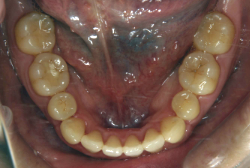

凸凹な歯並びのことを叢生といいます。矯正歯科に来院する患者様の主訴の中で、最も多いのが「配列の凸凹を真っ直ぐにしたい」というものです。歯の大きさと顎の大きさの調和がとれていないことが原因です。

凸凹を主体としたケースの場合、当院の平均治療期間は18ヶ月ですので、このケースは少し長めに経過しました。理由の一つは凸凹の程度がかなり重症だったと言うことですが、もう一つは、右下第2大臼歯が45度くらい前傾していたため、それを整直化させるために時間を要したと考えています。いずれにしても最終結果は大変よい状態と思います。

治療前は並びが乱れて見た目が悪いというのはもちろん問題ですが、歯科医学的に一番困るのは噛み合わせが悪いという点です。上下の犬歯(3番目の歯)は、上下的に離れた位置にあるため接触することができません。つまり歯としては存在していても、歯としては機能していないということです。